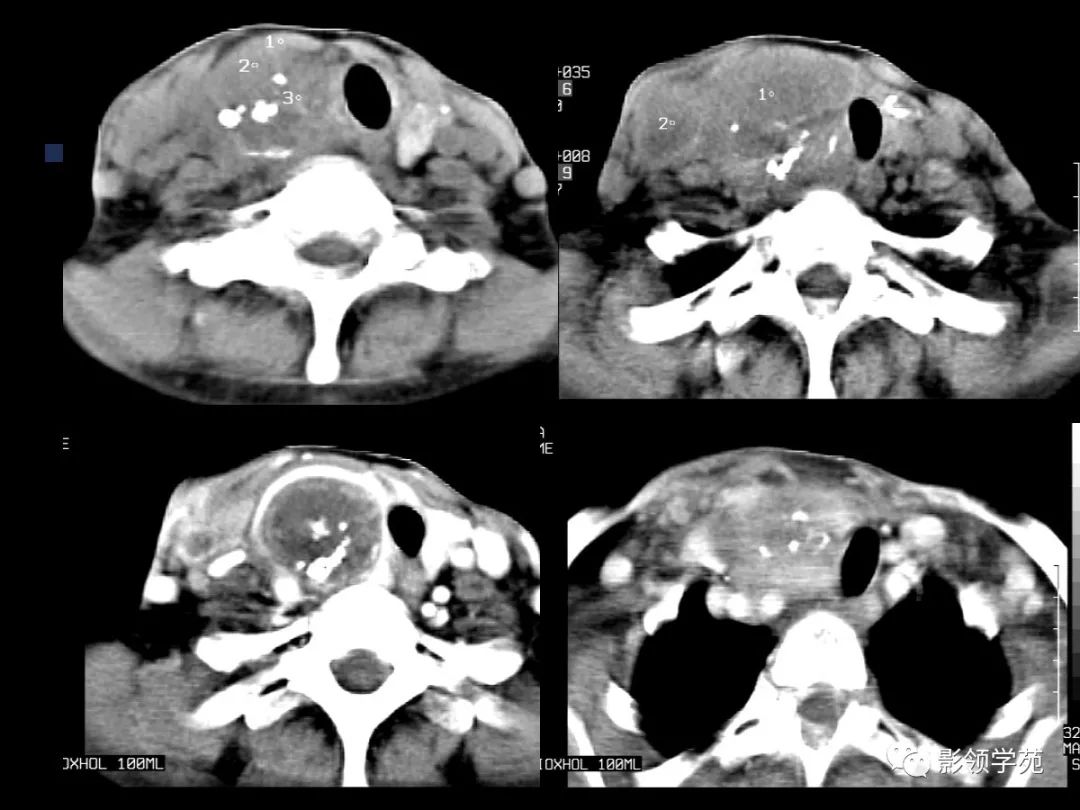

- MRI上实性肿块在T1WI上呈等低信号,在T2WI上呈高信号,囊变区呈长T1长T2信号,钙化在T1WI及T2WI上均呈低信号。

- 甲癌晚期肿瘤常突破甲状腺被膜向周围侵润

- 在增扫时可见环状强化。

- 由于CT和MRI能增强扫描可以清晰显示甲癌的侵润范围和程度,以及显示淋巴结的转移情况

- 手术前分期,指导治疗计划